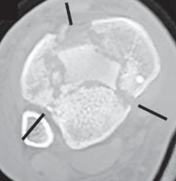

22.

Cole et al3 mapped 38 consecutive AO/OTA 43-C3 (complex articular) plafond fractures with CT scans and found that all plafond fractures in this category exited the tibiofibular joint laterally and at two separate locations medially to create a coronally oriented Y pattern with three major fragments ( FIG 2A). There were also varying amounts of articular comminution anterolaterally or anteromedially (FIG 2B).

--- A B ### FIG 2 • A,B. CT images from 43-C3 plafond injuries demonstrating typical fracture patterns with anterolateral, medial malleolus, and posteromedial fragments. Variable amounts of central or anterocentral articular impaction and comminution are commonly seen.

1. Isolated osteochondral fragments of variable size are often encountered (typically central to anterolateral in location; Fig 2B) and constitute the remaining portion of the articular surface.